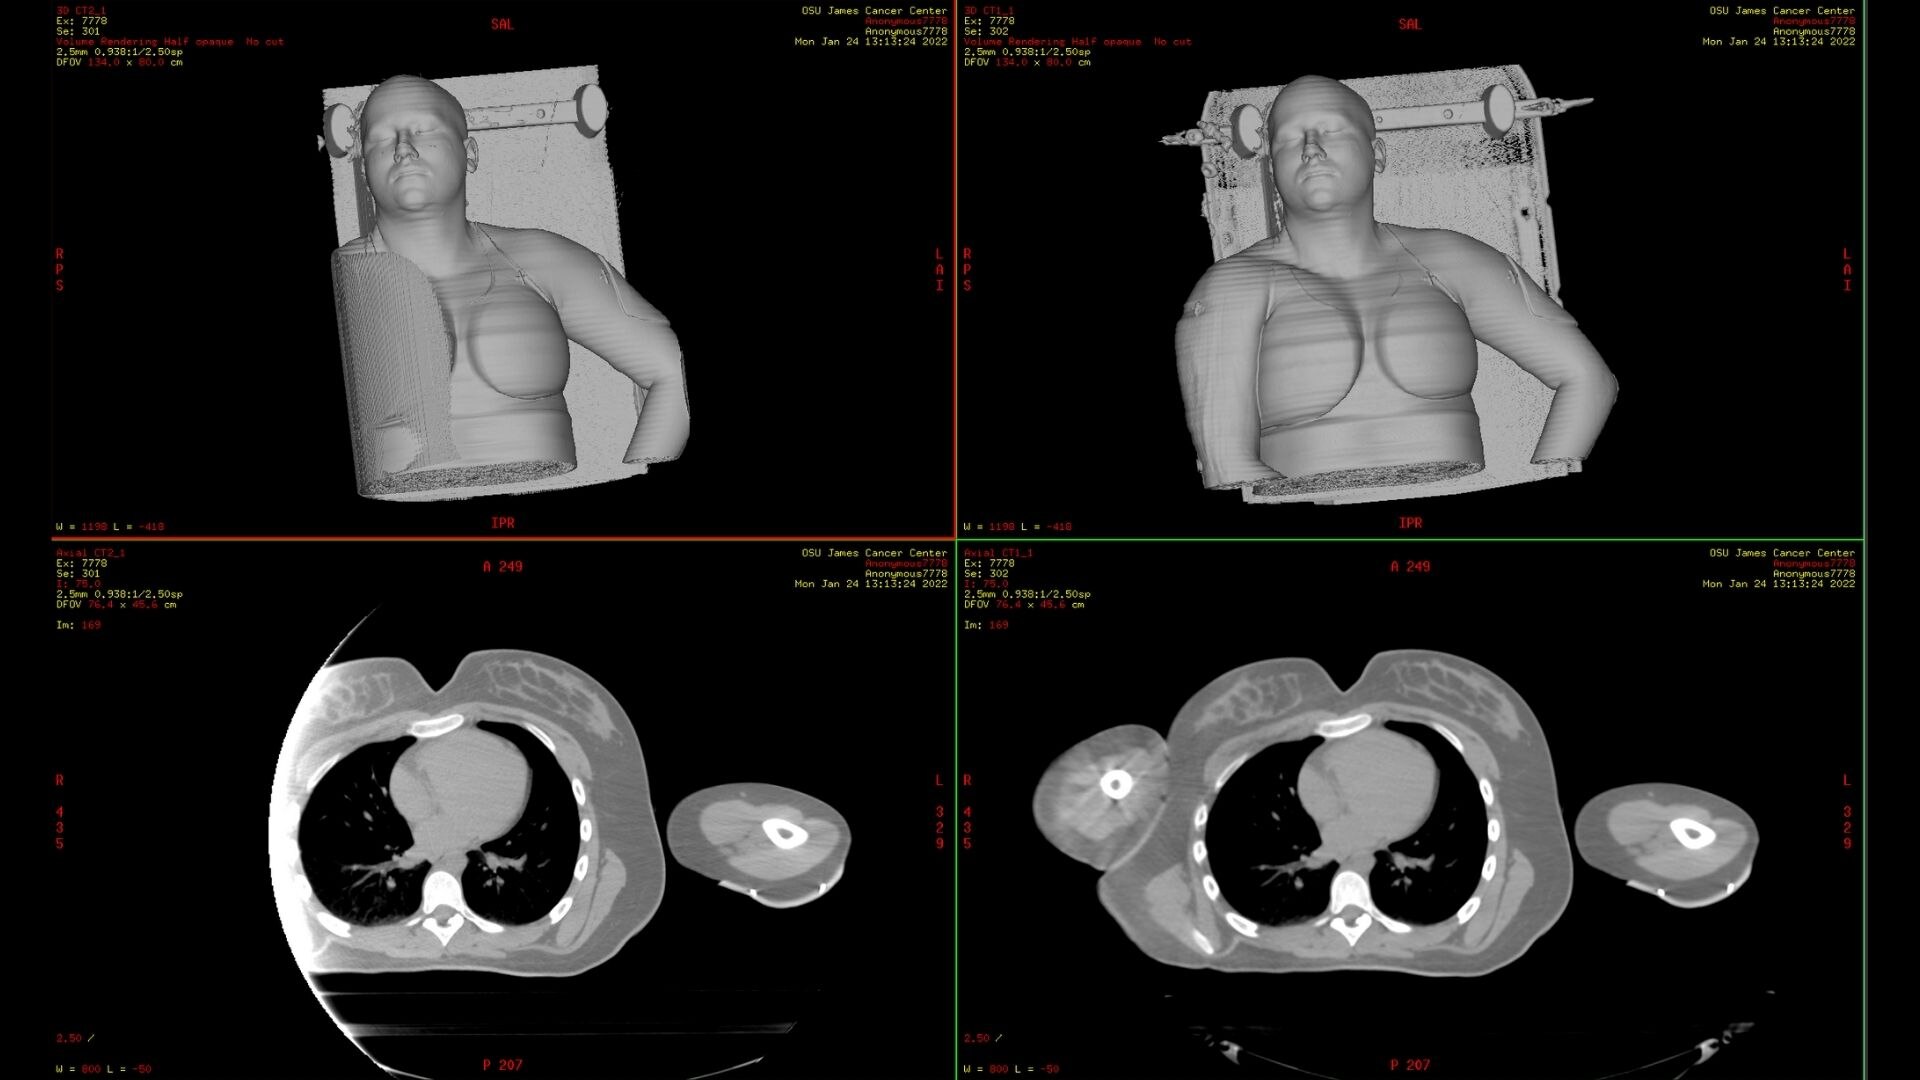

MaxFOV 2

The unique needs of radiation oncology make it important to have image data across the entire bore of the CT simulator. MaxFOV 2 uses GE HealthCare’s proprietary deep learning algorithm to build an extended view up to the edge of the bore. With up to 80 cm extended Display FOV (DFOV), MaxFOV2 allows for less limitations and better image quality that include:

• 2mm skin line accuracy and 40HU CT number accuracy of water from 50cm to 70cm DFOV *

• 3mm skin line accuracy and 60HU CT number accuracy of water from 70cm to 80cm DFOV *

*As demonstrated by phantom testing